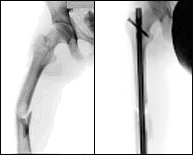

Fracturas de fémur

Nos referimos en este apartado a la porción media del fémur, a su diáfisis. Las fracturas a este nivel se asocian frecuentemente a traumatismos de alta energía como accidentes de tráfico o caídas desde grandes alturas y suelen acompañarse de fracturas a otros niveles constituyendo lo que denominamos politraumatismo. Se han descrito también fracturas de estrés en atletas de competición después de sobreesfuerzo repetitivo pero son muy poco frecuentes. El tratamiento es eminentemente quirúrgico proponiéndose un tutor intraóseo ubicado con una mínima incisión (menos de 3 centímetros) con la finalidad de quitar el dolor, restituir la longitud del muslo e iniciar cuanto antes el movimiento.